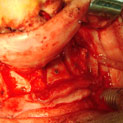

Existen muchas situaciones donde la pérdida y la atrofia ósea son tan graves que nos obligan a recurrir a la cresta iliaca del paciente, para conseguir el volumen óseo necesario para la correcta reconstrucción del maxilar. Así, la colocación de implantes será posible a los 3 meses.